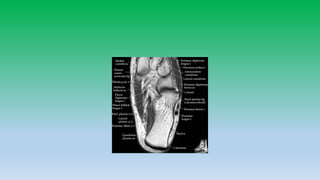

Medial ankle tendons:

• Tibialis posterior attaches to navicular , cuniform and base of 1st-4rt

metatarsal. Tibialis posterior tendon provides support to longitudinal

arch of foot and injury can cause flat foot.

• Flexor digitorum longus passes lateral to tibialis posterior tendon and

inserts to distal phalanges of 2nd-5th toes.

• Flexor halluces longus passes beneath sustentaculum talus and insert

into base off 1st toe distal phalanx. Sheath of FHL tendon

communicates with ankle joint and fluid within sheath is common.

Medial aspect

Tendon: Tibialis posterior

Flexor digitorum longus

Flexor H. longus

Ligaments: Deltoid ligament

• 12. Medial ankle tendons: • Tibialis posterior attaches to navicular , cuniform and base of 1st-4rt metatarsal. Tibialis posterior tendon provides support to longitudinal arch of foot and injury can cause flat foot. • Flexor digitorum longus passes lateral to tibialis posterior tendon and inserts to distal phalanges of 2nd-5th toes. • Flexor halluces longus passes beneath sustentaculum talus and insert into base off 1st toe distal phalanx. Sheath of FHL tendon communicates with ankle joint and fluid within sheath is common.

• 14. Medial aspect Tendon: Tibialis posterior Flexor digitorum longus Flexor H. longus Ligaments: Deltoid ligament